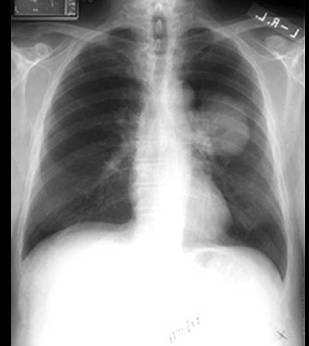

胸部X线片

>孤立性肺结节

-可表现为边界清楚的、圆形肺阴影

-直径<3cm -边缘毛刺或不清

-厚壁空洞

-所有类型的钙化表现倾向于良性病灶,除偏心性或散在点状钙化外

>肺门肿块

-中央型肺癌表现为肺门区域阴影

-淋巴结转移表现为肺门肿块突向周围肺组织

>阻塞性肺炎

-节段性或非节段性分布的密度不均或斑片状实变

-空气支气管征和空气肺泡征可发生于腺癌和支气管肺泡癌

>支气管狹窄

-支气管病灶常导致部分或完全肺叶不张

-常由非小细胞癌腔内生长导致

-可发现主支气管狭窄或完全堵塞

>纵隔淋巴结肿大

-纵隔增大

-右侧气管旁条纹影增加

-纵隔边缘凸起

-主肺动脉窗凹面消失

-隆突分叉增大

注:因CT扫描的普及现较少使用X线片